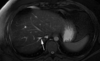

5

Q

A

left hepatic duct